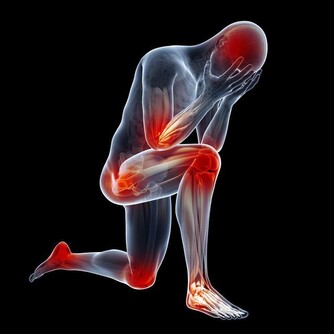

1、改善肩頸僵硬,加速了酸毒排出;

5、改善腰肌勞損,加速肌肉裡乳酸的排出;

8、排出尿酸,改善痛風,嘌呤偏高時就是關節受罪時;